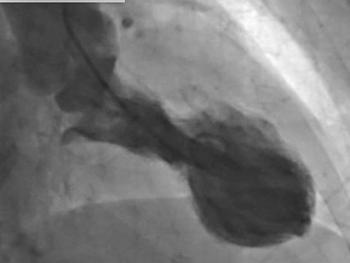

What is this seen post bypass surgery along the aorta?